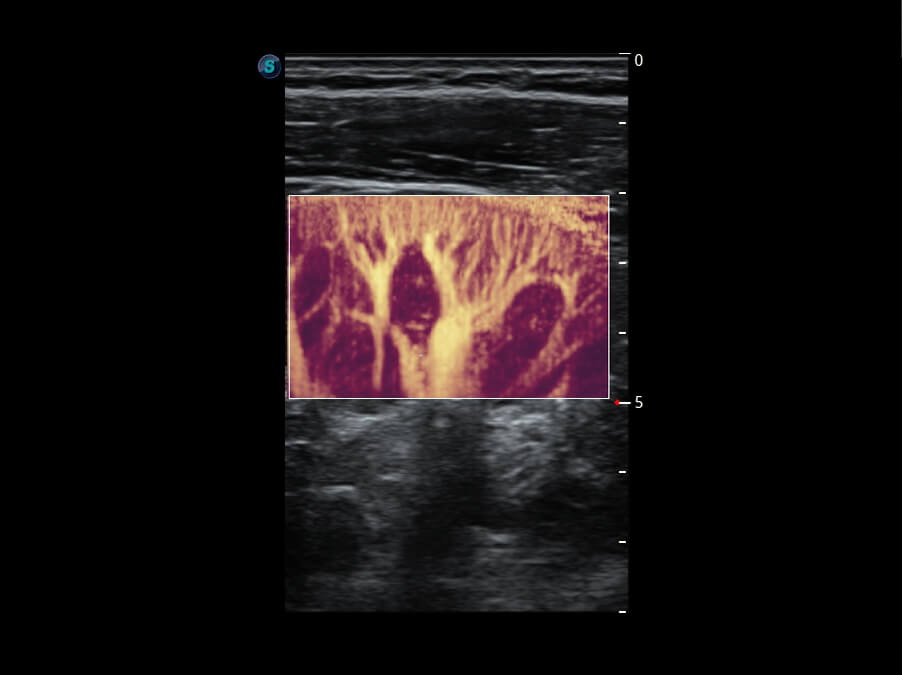

成像功能

S60探头工艺,从前端信号处理每一个环节采集无损声学数据,真实还原组织原貌,再现解剖细节。

超宽频带技术,为容积成像带来优质的二维图像基础,为您呈现丰富的结构细节,栩栩如生地展示宝宝的宫内形态以及各种组织的立体结构。